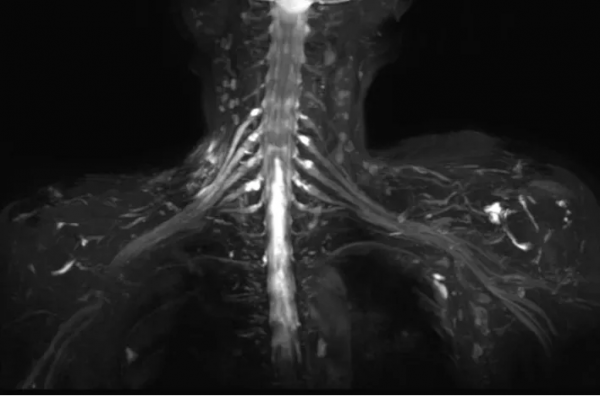

近日,遼寧省腫瘤醫院醫學影像科開展了一項新技術——3.0T磁共振神經成像。此項技術主要應用於臂叢及腰骶叢神經顯像,可以清晰顯示臂叢及腰骶叢神經全貌及周圍結構關係,椎管內及椎間孔區神經根結構。此技術的開展將為臨床診斷臂叢神經損傷、神經鞘瘤、放射性臂叢神經炎提供可靠資訊,同時為腫瘤患者術前診斷及術後長期隨訪提供重要的資訊。

新技術適用病例1:女,65歲,右乳癌術後18年,右頸及上臂疼痛2年。右側臂叢遠端受壓。